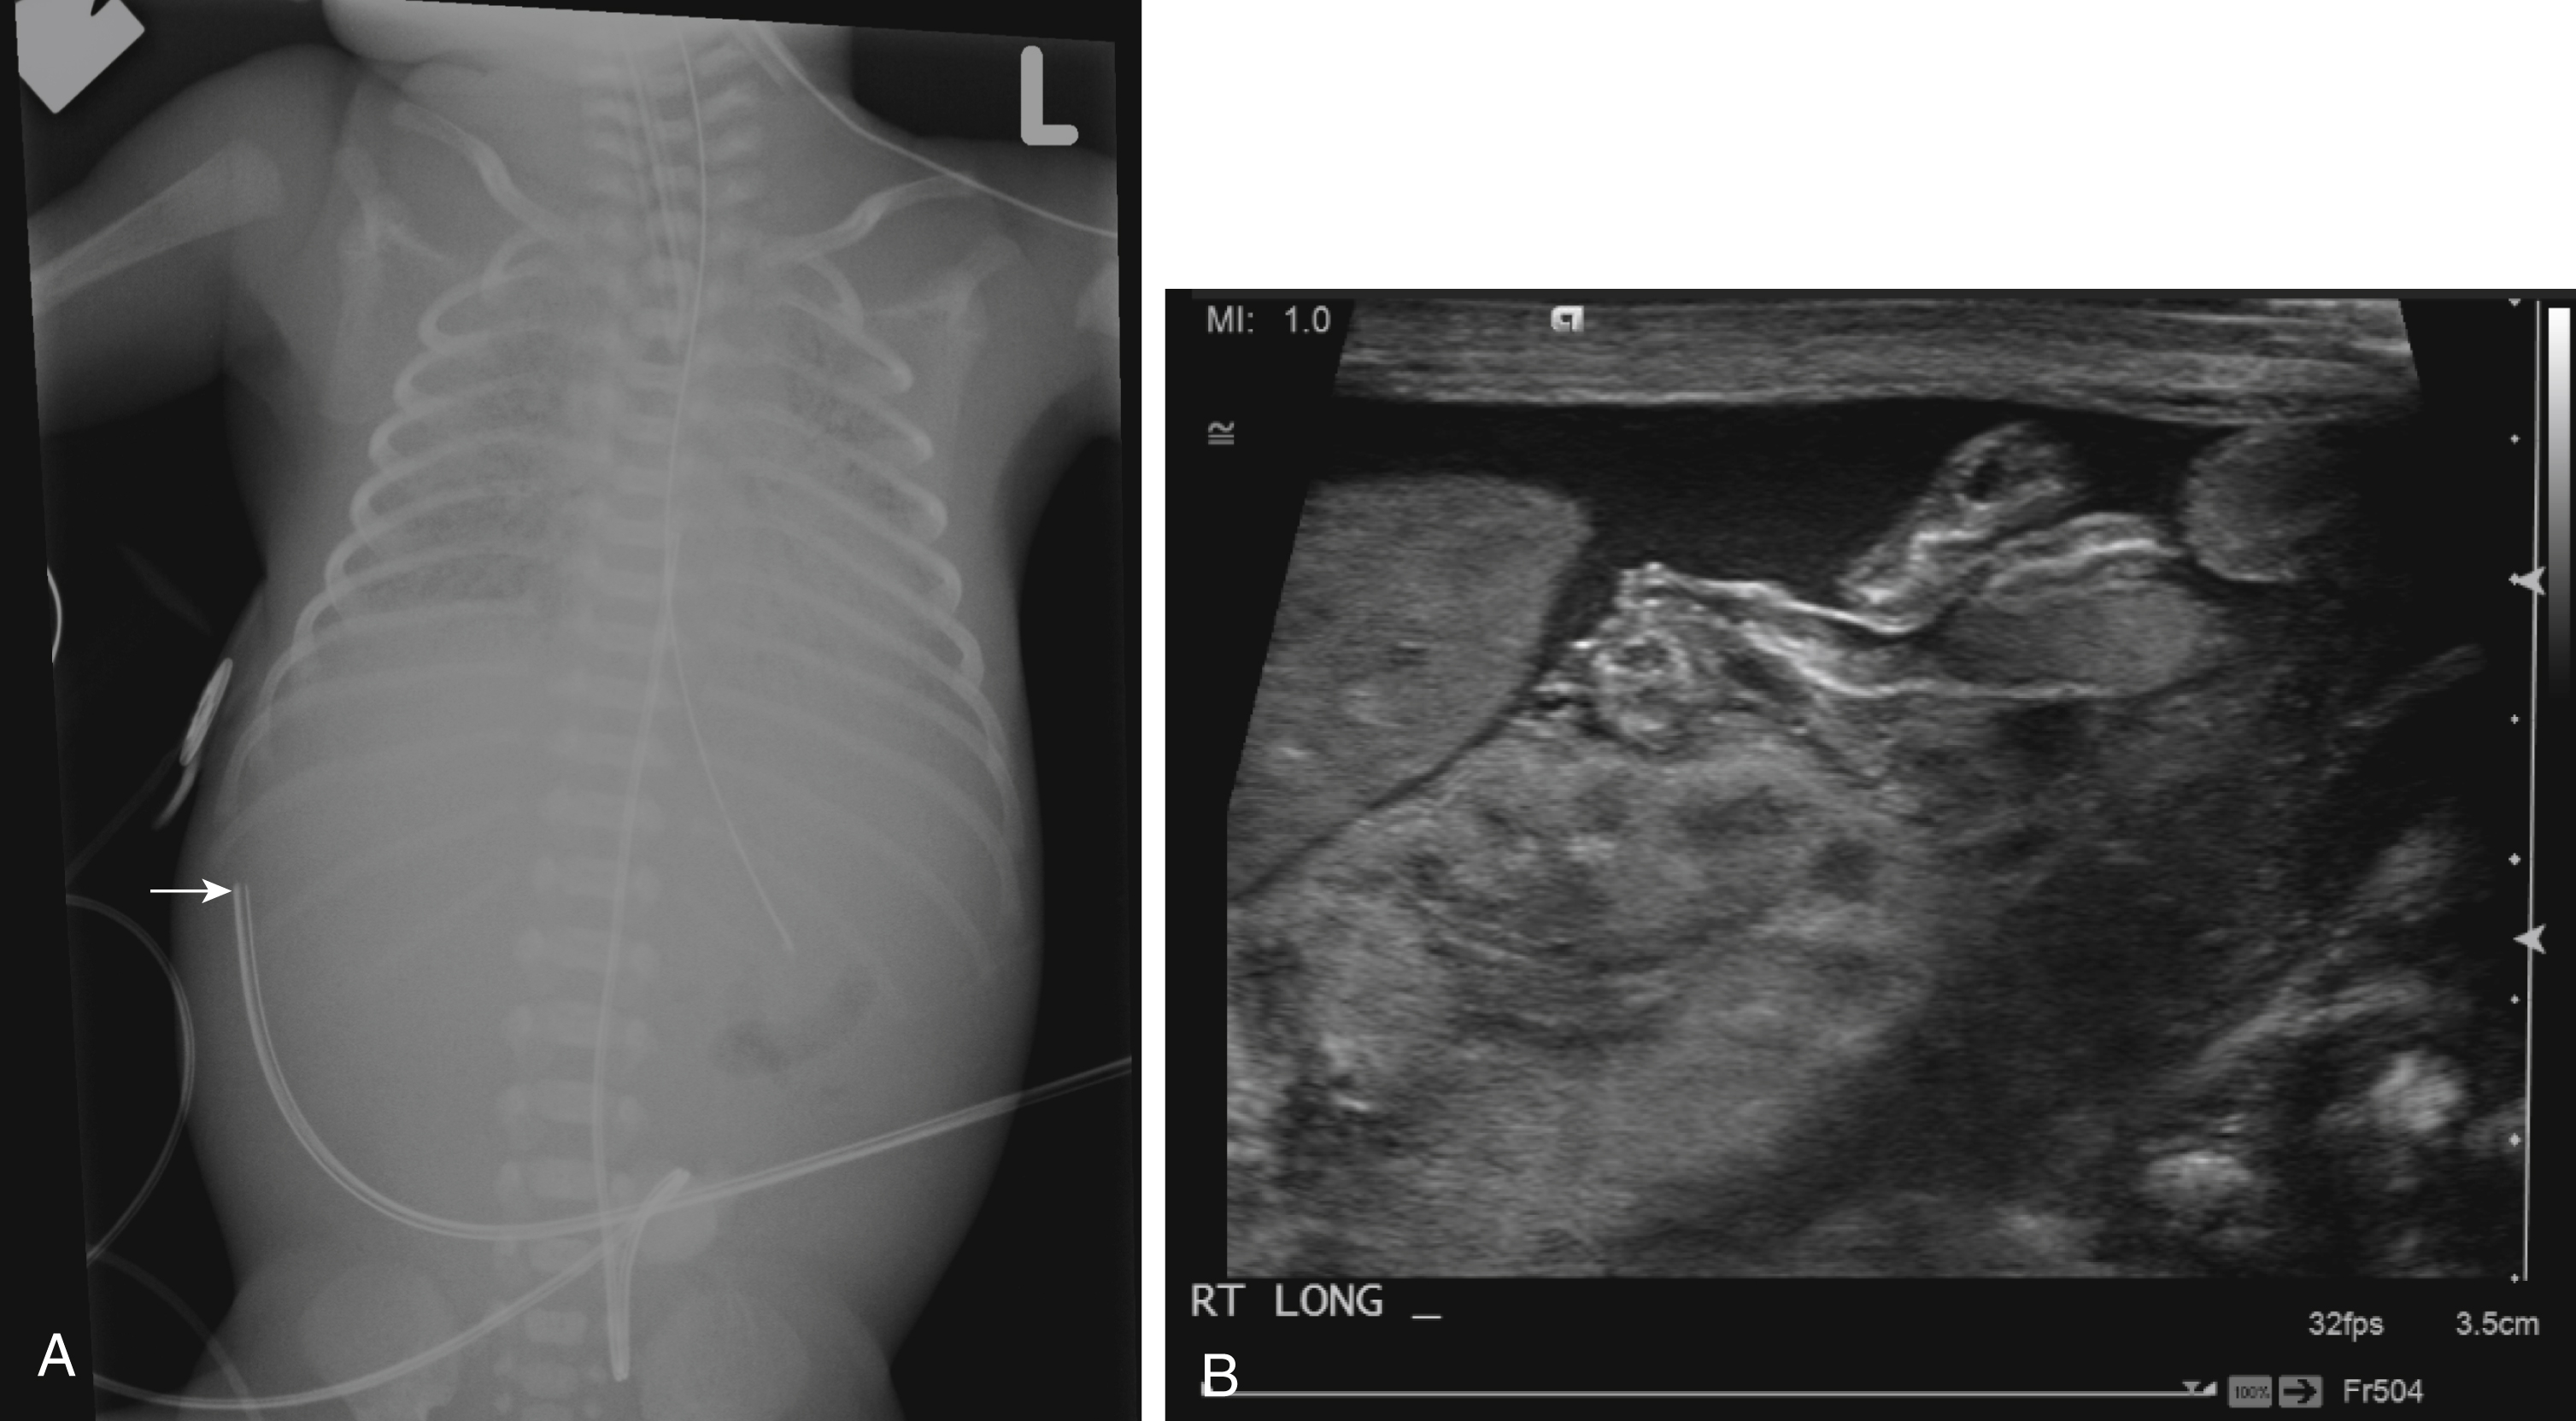

Because of lack of imaging guidance during UVC placement, misplacement is not uncommon ( Fig. 18.2 ). Complications of UVC misplacement include hepatic hematoma and necrosis in the setting of an intrahepatic placement of a UVC ( Fig. 18.3 ), right or left atrial perforation, or umbilical vein perforation resulting in extravasation or hemoperitoneum ( Fig. 18.4 ). Thrombosis in the inferior vena cava may occur even in an appropriately positioned UVC.

Fig. 18.3, Umbilical venous catheter malposition.

Fig. 18.4, Umbilical venous catheter malposition.